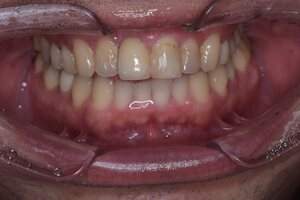

口腔内写真

- Before

- 途中経過

- After

| 年齢 | 60代・女性 |

|---|---|

| 主訴 | 左下6番、7番 歯ぐきの腫れが気になり来院。 歯周病がかなり進行しており骨がほとんどない状態で動揺もあった。 |

| 治療内容 | インプラント治療 動揺がひどく歯を残すことが難しいため抜歯へ。 その後骨造成を行いインプラントを埋入。 |

| 治療費 | 合計:1,683,000円 内訳 診断料:55,000円 埋入料:165,000円×2本 チタンメッシュ:55,000円×2本 GBR:110,000円×2本 サージカルガイド:66,000円 静脈内鎮静麻酔:77,000円×2回 2次オペ:22,000円×2本 仮歯:55,000円×2本 上部構造(フルジルコニア):187,000円×2本 APF(歯肉弁根尖側移動術):110,000円×2本 (2024年1月現在) |

| 治療期間 | 16ヶ月 |

| リスク・副作用 | インプラントはご自身のセルフケアに加え、歯科医院でのメインテナンスが不十分だと、歯周病になることがある。 歯ぎしり、食いしばりが強い方はインプラントの上部構造が割れてしまうことがあるため、就寝時にマウスピースの使用が必要。 |

| 治療方針 | 歯周病がかなり進行していて骨吸収がみられるのでチタンメッシュと骨補填材を使った骨造成が必要。 先に骨造成を行い骨が再生されるのを待って埋入手術を行う。 歯ブラシがしやすくなるようにAPF ( 歯肉弁根尖側移動術 )も行う。 |

| 特記事項 | 今回は印象材ではなく光学スキャナーを使用して型どりを行った。 |

| 担当者所見 | 骨が再生するか難しいところだったが無事埋入でき問題なく結合できた。 また今回は印象材ではなく光学スキャナーを使用して印象したため患者さまの負担がかなり軽減されたと思う。 上部構造セット後しっかりとかめている。 今後も定期的にメインテナンスしていく。 |